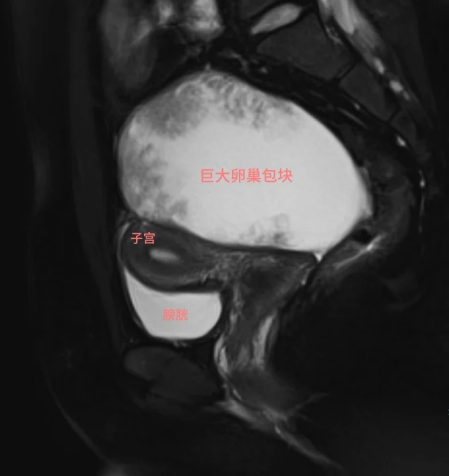

当超声论说上出现“右侧卵巢10cm+肿物、囊实性转变、血流信号丰富”这些字眼时,小西被见知还需要立即去抽一些血和完善盆腔MRI查验。情况可能莫得黄体突破这样陋劣。

盆腔MRI影像

当今盆腔MRI和全腹CT指示,卵巢上皮起原恶性肿瘤的可能性较大,但还没发现彰着移动灶,粗略还有保留生养功能的契机。